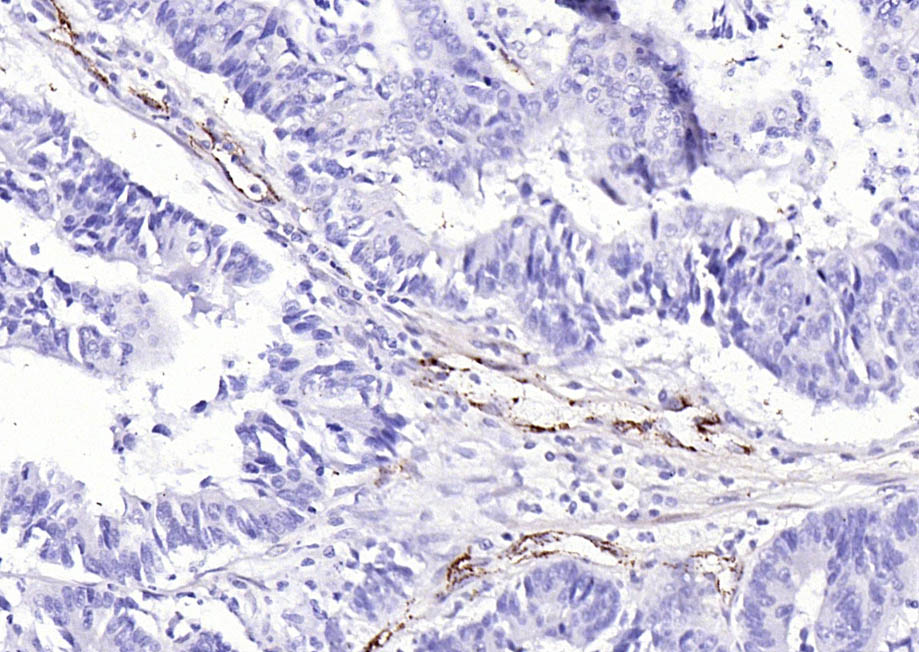

Paraformaldehyde-fixed, paraffin embedded (human lung carcinoma); Antigen retrieval by boiling in sodium citrate buffer (pH6.0) for 15min; Block endogenous peroxidase by 3% hydrogen peroxide for 20 minutes; Blocking buffer (normal goat serum) at 37°C for

Paraformaldehyde-fixed, paraffin embedded (human colon carcinoma); Antigen retrieval by boiling in sodium citrate buffer (pH6.0) for 15min; Block endogenous peroxidase by 3% hydrogen peroxide for 20 minutes; Blocking buffer (normal goat serum) at 37°C for